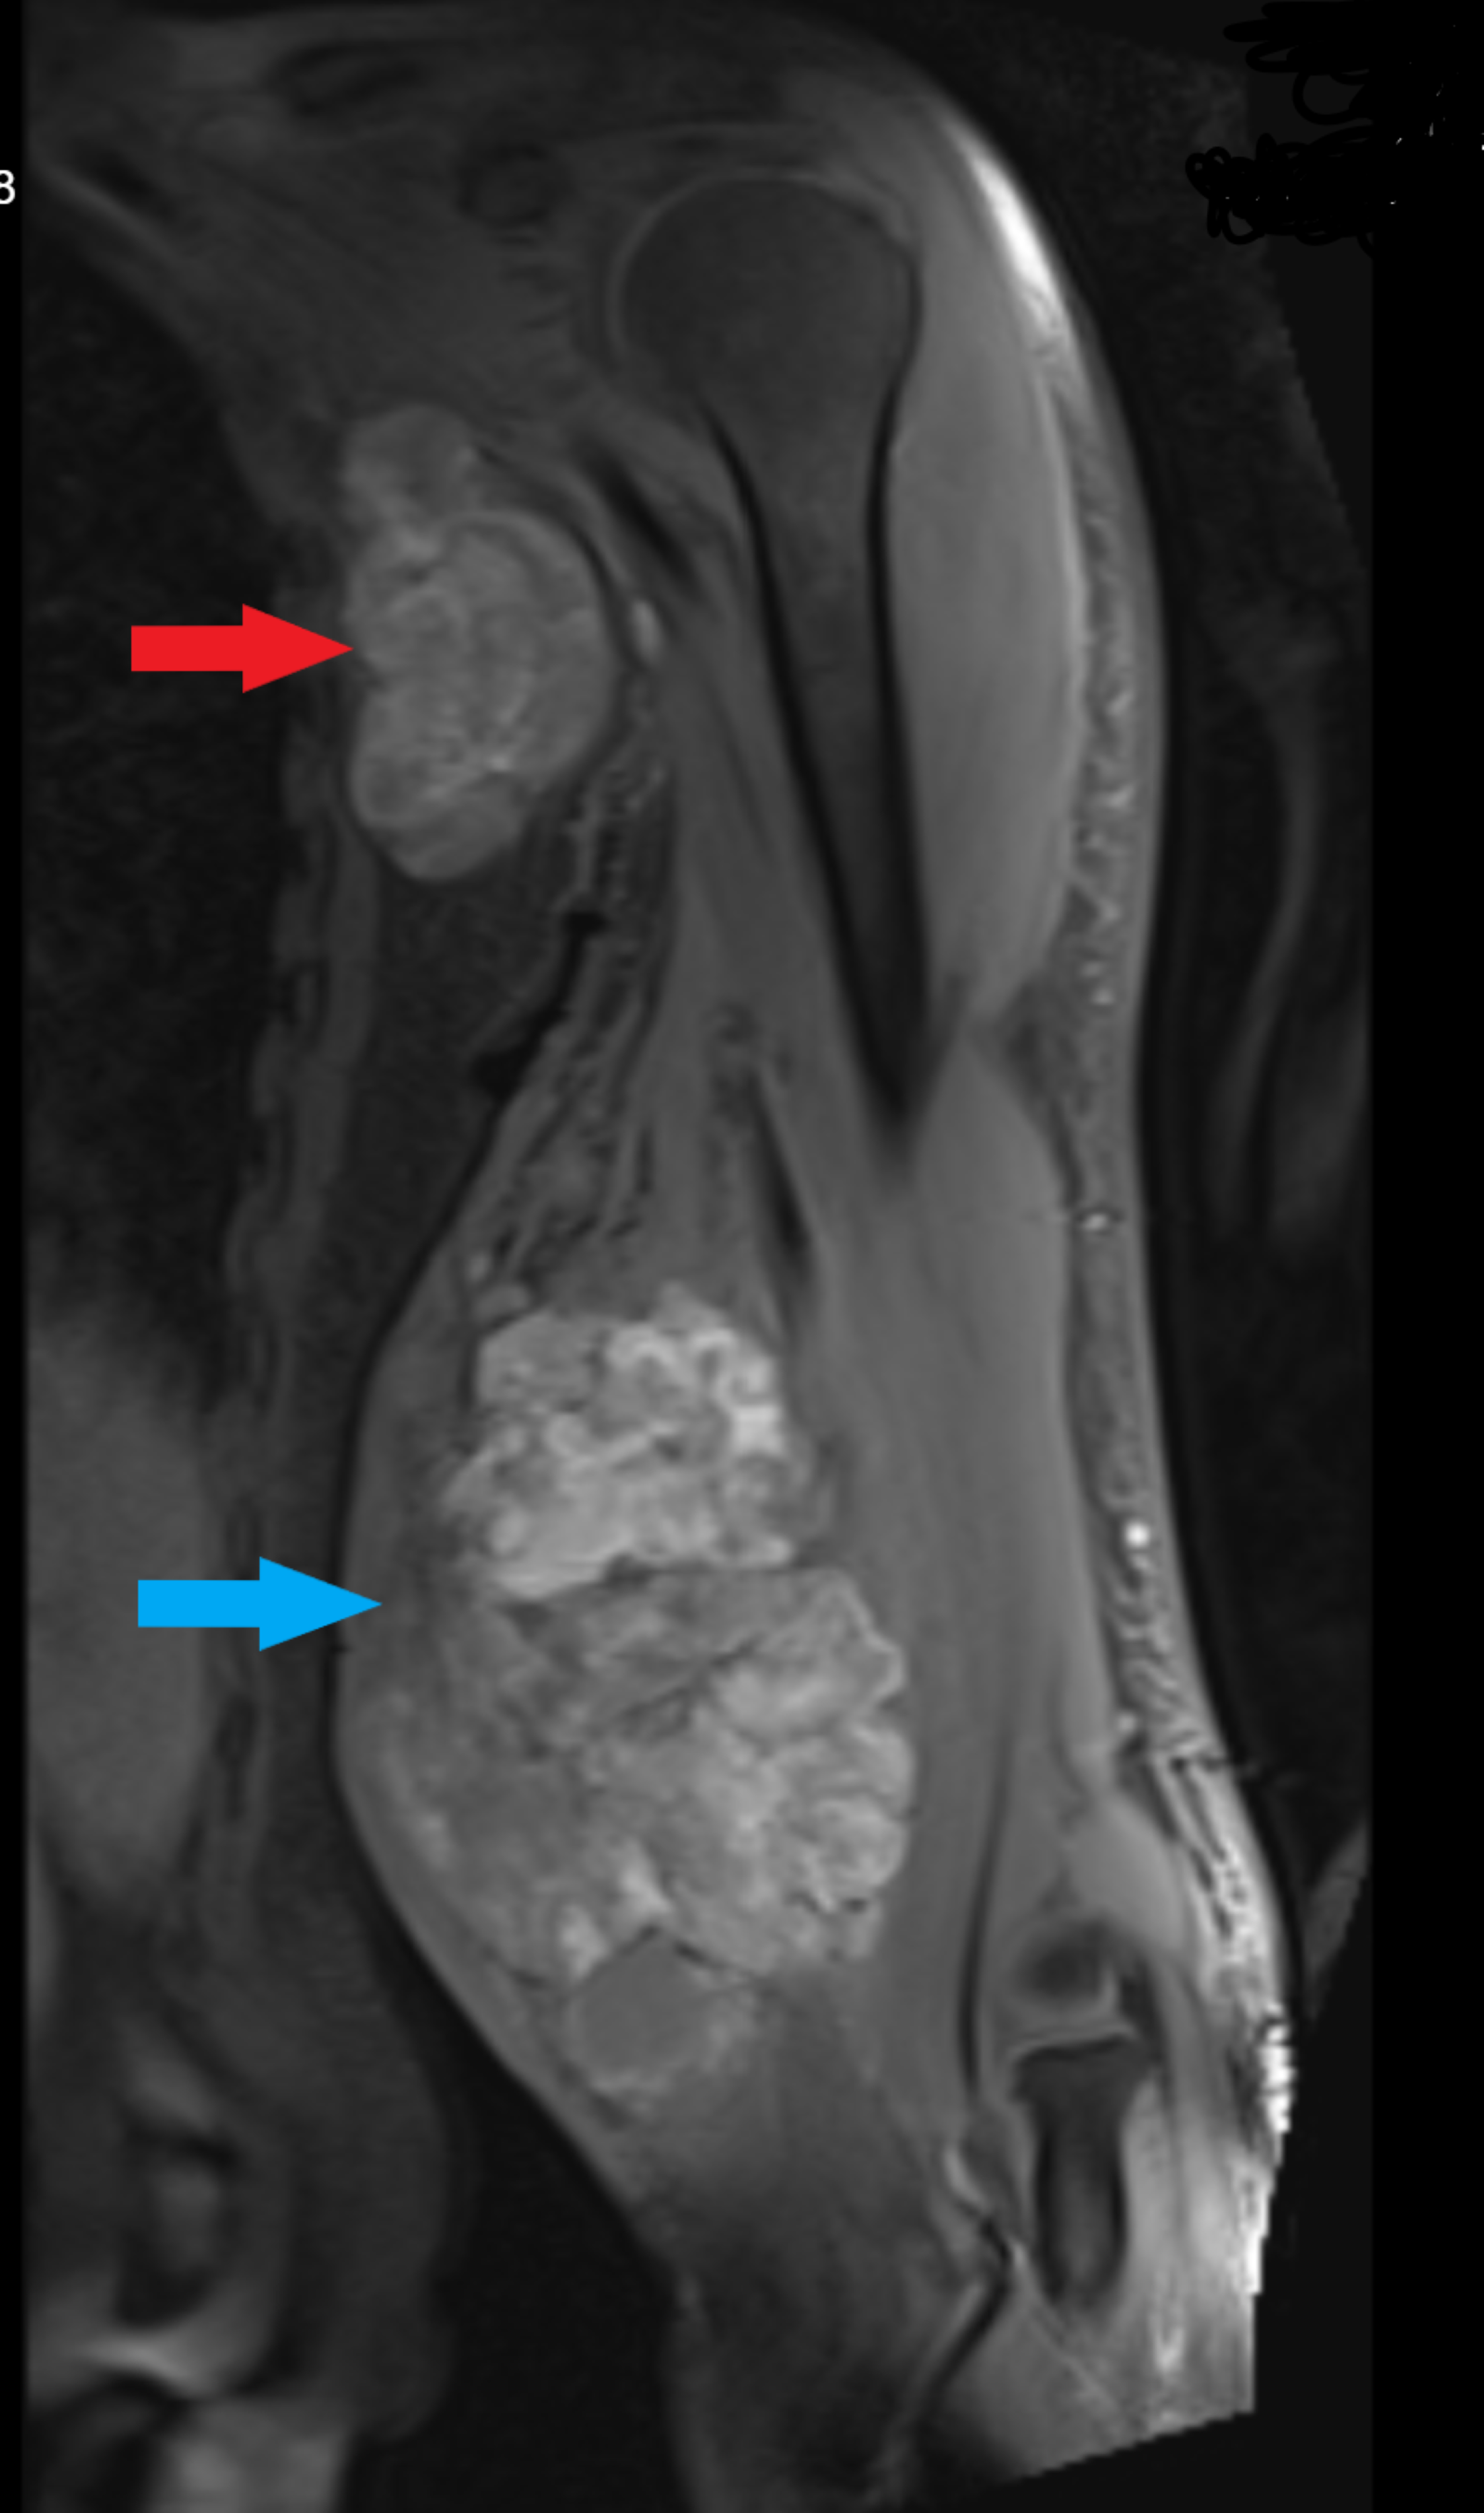

Breast MRI in a patient with rightsided multicentric breast cancer Pump Bump Mri Haglund deformity, also known as a pump bump, bauer bump, or mulholland deformity, is defined as bony enlargement formed at the. It is also known as retrocalcaneal exostosis, mulholland deformity, and ‘pump. Sometimes it's called “pump bump” because the deformity often occurs in. Because of its prominence, the bump is subject to constant friction, causing redness, pain, swelling, and calluses.. Pump Bump Mri.

MRI finding for nontriple negative breast cancer in 46 yearold woman Pump Bump Mri Haglund's deformity is a bony bump where your achilles tendon attaches at the back of your heel bone. Haglund’s deformity is sometimes called a “pump bump” because it’s especially painful to wear shoes like pumps (high heels) that have tight backs. Sometimes it's called “pump bump” because the deformity often occurs in. Haglund deformity, also known as a pump bump,. Pump Bump Mri.

A 57yearold female with a palpable left breast lump. MRI illustrates Pump Bump Mri Because of its prominence, the bump is subject to constant friction, causing redness, pain, swelling, and calluses. It is also known as retrocalcaneal exostosis, mulholland deformity, and ‘pump. Also known as a pump bump, it is usually caused by shoes repetitively rubbing against your heel. Haglund’s deformity is sometimes called a “pump bump” because it’s especially painful to wear shoes. Pump Bump Mri.